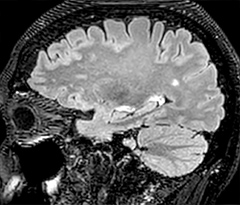

In this patient with acute right motor deficit and aphasia, the b2000 diffusion weighted image is normal. The SWIp image demonstrates more prominent veins in the right hemisphere, which could reflect increased deoxyhemoglobin contents. Fast ASL shows low CBF regions in the left frontal lobe. A follow-up ASL after one hour demonstrates high CBF values in the same area. The final diagnosis was migraine with aura.

Dr. Savatovsky appreciates the improvements and flexibility that Elition with Compressed SENSE and MultiBand SENSE provides, particularly for stroke patients. “For stroke, it allows us to cut about 5 minutes off of our stroke protocol, or to keep the same acquisition time and get more insights.” The ability to perform more sequences can help in making a swift and confident diagnosis. “For example, our stroke cases usually include the regular sequences that every center does (b1000 diffusion, FLAIR, time-of-flight angiography), but we also image supra aortic vessels, and we can replace a gradient echo sequence with a fast 50-second susceptibility-weighted sequence, and all of this doesn’t add much time. because all the regular sequences are accelerated on Elition.” “The time savings with Compressed SENSE and MultiBand SENSE make it easier to add sequences to give us additional insights. Depending on the context and the first results, we might add a DSC perfusion to assess the ischemic penumbra, an ASL perfusion to help find an alternative cause in case of normal diffusion, or add a high-resolution T1 sequence for a stroke patient, to quickly assess wall imaging in emergency cases. The additional sequences can help improve patient management, because we can already consider some alternative diagnoses if the morphological MRI is normal.”